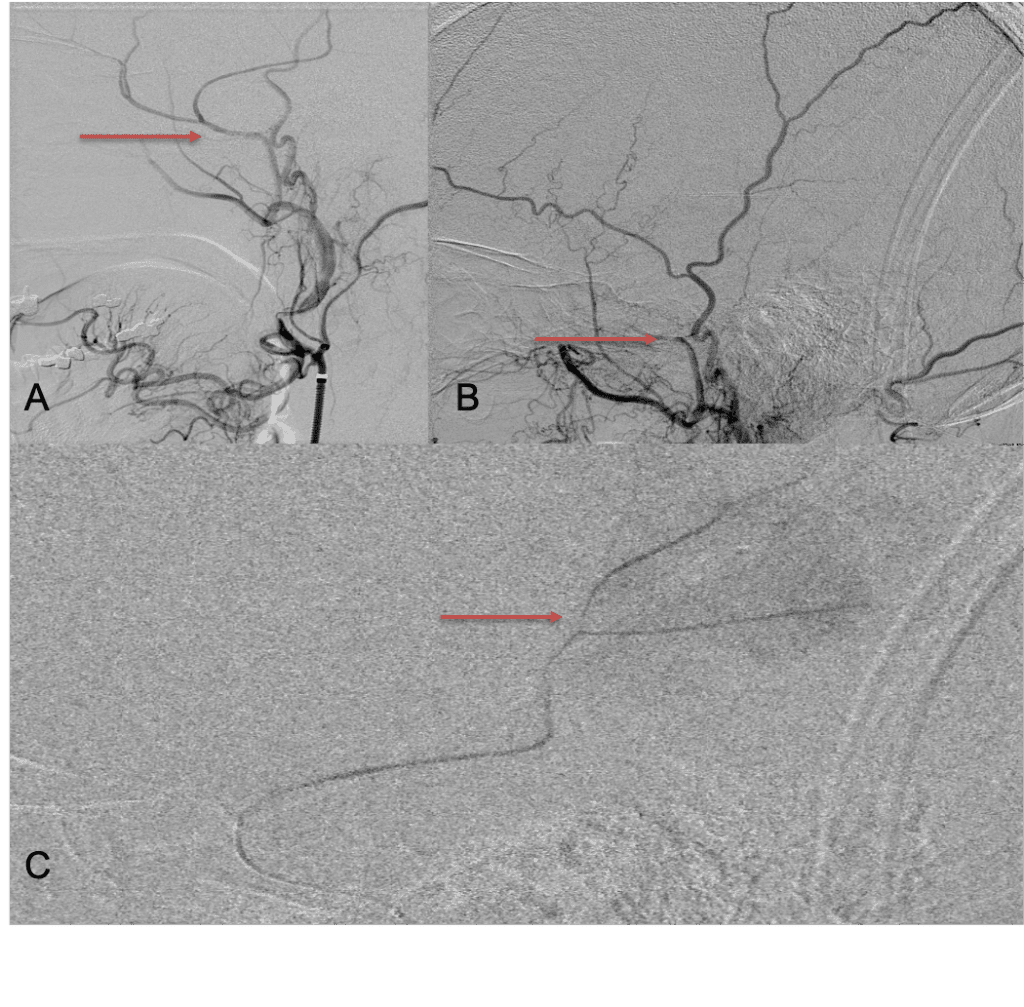

The patient agreed to receive minimally invasive treatment with Bilateral Middle Meningeal Artery Embolization, a new approach to promote resorption of chronic and subacute subdural hematomas in patients that are not improving with conservative measures or have contra-indications to surgical evacuation. Selective catheterization of the Middle Meningeal Artery is followed by transarterial embolization of the territory and inflammatory membranes that are felt to be secreting serosanguinous proteinaceous exceeding the capacity for resorption. MMA embolization was performed bilaterally in this patient. (Figure 2. A and B)

Figure 2. A) Initial right ECA angiogram ; B) Post MMA Embolization; C) Selective Embolization Of Middle Meningeal Artery Membranes using PVA particles (arrows).

CT follow-up at 1 week demonstrates early resorption. 2 weeks post MMA embolization, resolution of the left subdural collection with new small thin acute hemorrhage in an otherwise stable right subdural collection is observed (Figure 3. A and B).

Figure 3. A) 1 week post MMA embolization demonstrating decreasing thickness bilaterally B) 2 weeks post MMA demonstrates resolution on left, with small new acute component on right with overall decreased thickness.